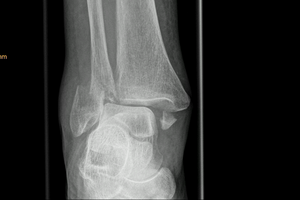

Brüche des oberen Sprunggelenks (OSG) sind die häufigsten Frakturen der unteren Extremität. Das obere Sprunggelenk besteht aus dem Waden- (Fibula), dem Schien- (Tibia) und dem Sprungbein (Talus). Schien- und Wadenbein formen eine Gabel, in welcher sich das Sprungbein bewegt. Die Stabilität des knöchernen Sprunggelenks wird durch Bänder (Außenbänder, Innenband und Syndesmose) gewährleistet. Sprunggelenks-Frakturen können sehr komplex sein und aus einer Reihe von Kombinationsverletzungen des Außenknöchels (Malleolus lateralis), Innenknöchels (Malleolus medialis), der Hinterkante des Schienbeins (posteriorer Malleolous) und der Bänder bestehen. Entsprechend der Anzahl der betroffenen Knochen unterscheidet man zwischen einer isolierten Außenknöchelfraktur, einer Bimalleolar- (Außen- und Innenknöchel) und oder einer Trimalleolar-Fraktur (Außen-, Innenknöchel und Schienbein-Hinterkante).